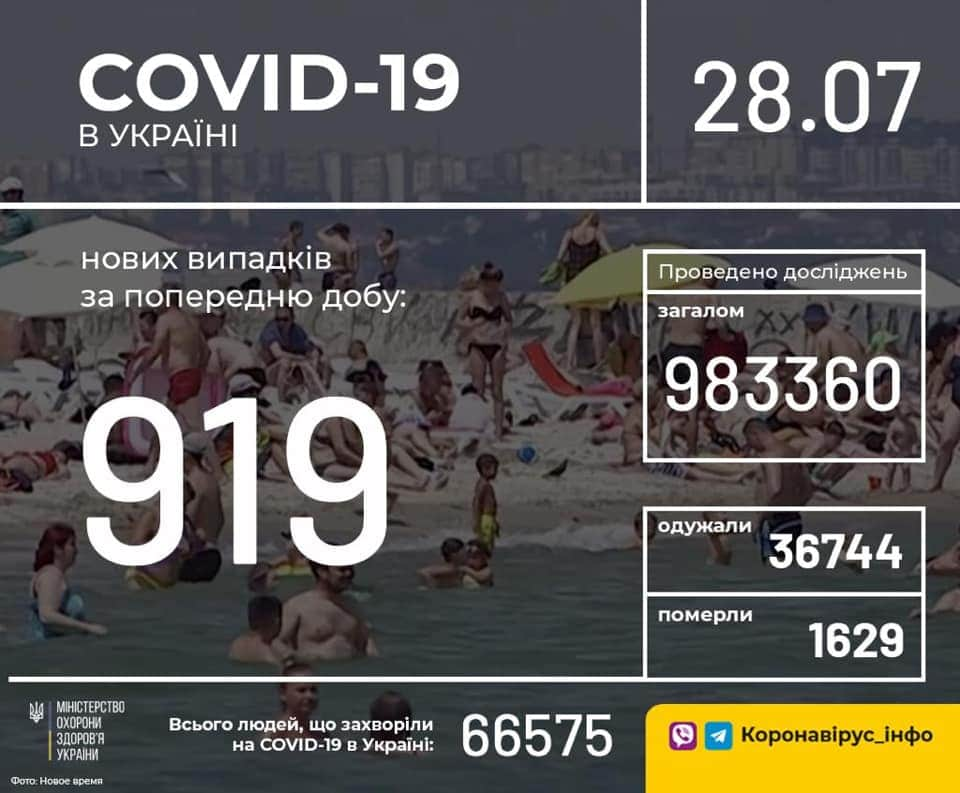

Більше 3 тисяч випадків захворювання на коронавірус зафіксували в Україні за добу

11.09.2020 09:37